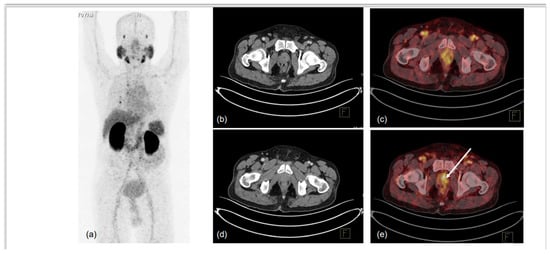

5. Biochemical Recurrence and Metastatic PCa